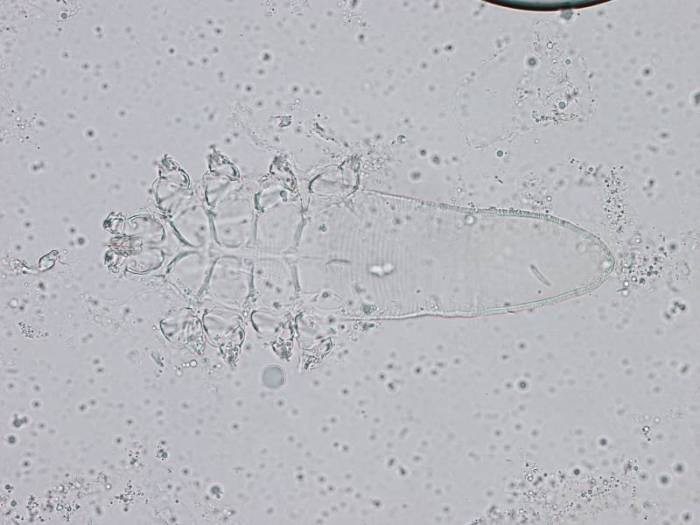

Для определения подкожного клеща у кота берут соскобы с пораженных участков тела (не менее 4-5 проб) для дальнейшего изучения под микроскопом.

Обнаружение в соскобе хотя бы одного клеща Demodex gatoi дает право ветеринару поставить диагноз демодекоз. В случае с подкожным клещом Demodex cati ситуация другая. Этот клещ живет на каждой кошке. Диагноз ставится, если в одном соскобе обнаружено более 2-3 особей.